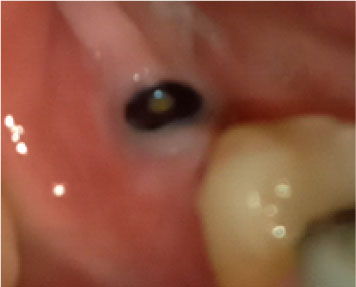

In terms of severity, Class I exposure was the most common with seven implants. Moreover, Class III was the least common with only one implant. The number of exposed maxillary and mandibular implants is presented in Figure 1. Also, Figures 2-6 show the exposure of maxillary premolar implants.

Figure 2. Class I exposure of a maxillary premolar implant.